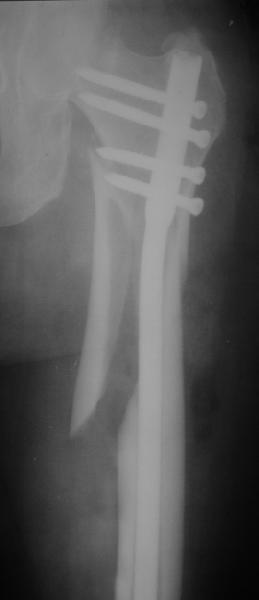

Женя, эта картинка показывает не оптимальное лечение вертельных переломов в моем представлении, а особенности дизайна упомяутого фиксатора.

В частности, его возможности при фиксации переломов проксимального отдела бедра - в сравнении с другими, имеюшими лишь по одному статическому и динамическому отверстию и с кондуктором для введения 2 винтов.

Это было года 2,5 назад, мы тогда еще уточняли возможности шинирования с угловой стабильностью гвоздем с поперечным расположением винтов при переломах проксимального отдела бедра. Пациенту не пришлось приобретать намного более дорогой рекон или проксимальный гвоздь. В приложении еще несколько примеров применения того гвоздя при высоких переломах бедра, в том числе с более латеральной точкой входа. Гвоздь изгибаем для этого.